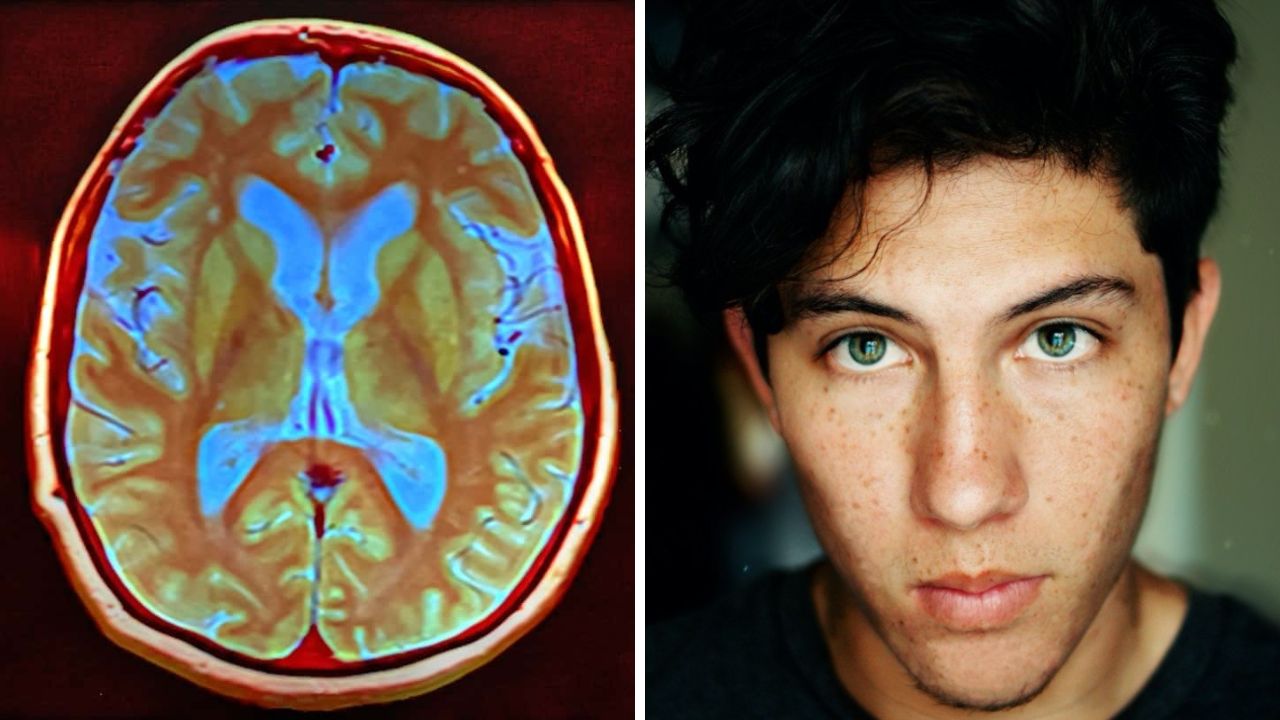

Chronický stres spôsobuje “zmenšovanie” mozgu

Stres si vyberá daň na tele, mysli a duchu a je v podstate jedno či sa jedná o akútny alebo chronický stres. Každý má svoje špecifické negatíva a najhoršia je kombinácia ich oboch. Avšak, pri chronickom strese sa pravidelne uvoľňuje kortizol, jeho hladina je teda nepretržite zvýšená a to má vplyv na funkciu mozgových neurónov, ktoré nemôžu efektívne fungovať, prípadne môžu ubúdať, čím sa akoby “zmenšovala” mozgová hmota.

PTSD (posttraumatický stresový syndróm) a ďalšie problémy spojené s prežitou traumou často zmenšujú hipokampus, oblasť mozgu, ktorá vytvára nové spomienky.